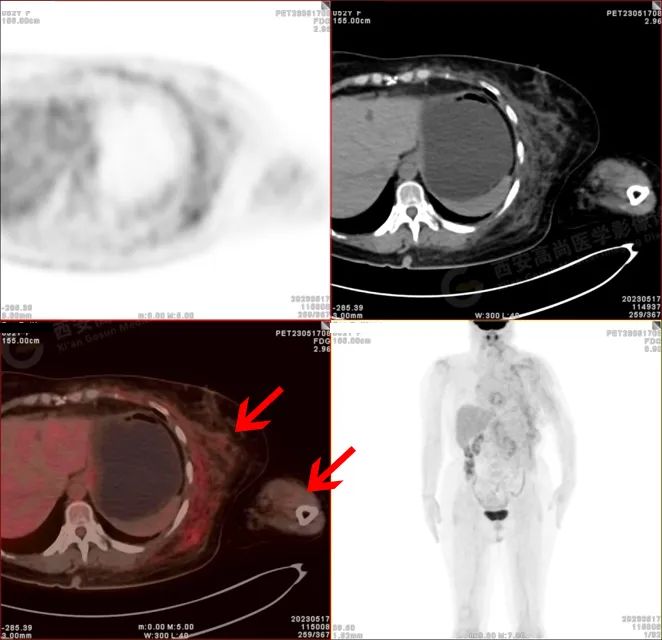

PET/CT 影像图

左侧上臂、颈 4-腰 4 椎体水平左侧颈、左侧肩部、左侧腋窝、左侧胸部(含左侧乳腺)、左侧腹部、左侧背部广泛区域皮下及肌肉区可见疏松、肿胀混杂密度软组织病变,边界模糊不清,相邻骨质结构完整,上述病变呈不均匀放射性摄取轻度异常增高,SUV 最大值介于 1.2-2.4。上述改变,符合韧带样纤维瘤病。